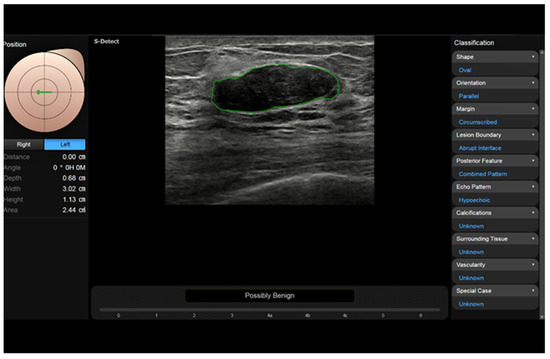

2.9. Computer-Assisted Diagnosis—S-Detect

Owing to deep learning algorithms, artificial intelligence systems are able to automatically detect and quantify a number of features from US images [16,68,83,84,85,86,87,88,89,90]. This may allow for the simple and reproducible detection and characterization of breast lesions as well as the prediction of the response to treatment in patients with locally advanced breast cancer. Computer-assisted diagnosis (CAD) can be employed as a second reader to improve the accuracy of the operator in US or CEUS imaging of the breast [64,91,92,93]. The software analyzes the targets identified by the operator, showing their shape and their risk of malignancy based on the BI-RADS lexicon or other descriptors. A CAD system works through four successive phases: pre-processing, segmentation, feature extraction and selection, and classification [64,94]. The analysis can be approved or rejected by the operator [95,96].

CAD systems can be offline, located in a personal computer, or inserted directly on the scanner. An example of the latter is represented by S-DetectTM, a semi-automatic tool from Samsung (Busan, Republic of Korea) [97,98,99,100]. The operator manually places a marker inside a lesion, and then, the software traces the border (adjustable) and analyzes and classifies the lesion according to the US descriptors from the BI-RADS (Figure 7).

In a study on the differential diagnosis of breast lesions, the sensitivity of five operators of different experience levels was >90% and specificity was 50–75%, while S-Detect had 90% sensitivity and 71% specificity [101]. Advanced systems are fully automatic, are based on convolutional neural networks, and have a high capability of recognizing the images.

Figure 7. S-Detect automatic measurement and categorization of a breast nodule (fibroadenoma) using BI-RADS descriptors.